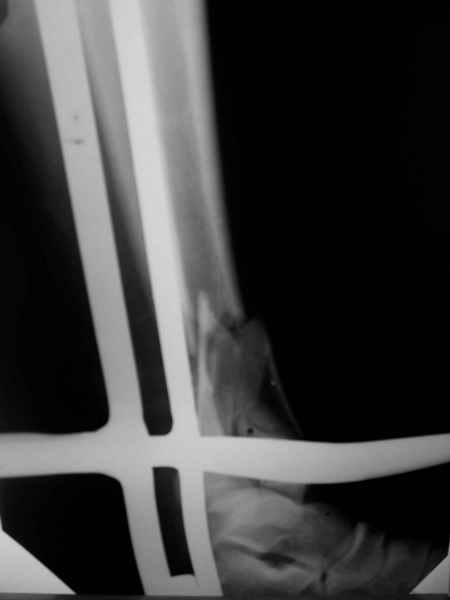

Открытый оскольчатый перелом н/3 голени. |

Здравствуйте, коллеги! 16/10/06 г. В отделение поступила больная с производственной травмой - Открытый оскольчатый перелом метафиза и метадиафиза обеих костей правой голени со смещением отлоков.

При поступлении произведено ПХО ран, наложена система скелетного вытяжения за пяточную кость. Проводилась антибактериальная терапия, перевязки. На данный момент раны зажили первичным натяжением, швы сняты. Сохраняется лёгкая гиперемия в области одной из ран. Планируя оперативное лечение хотелось бы узнать Ваше мнение о наиболее рациональном методе лечения данного перелома.